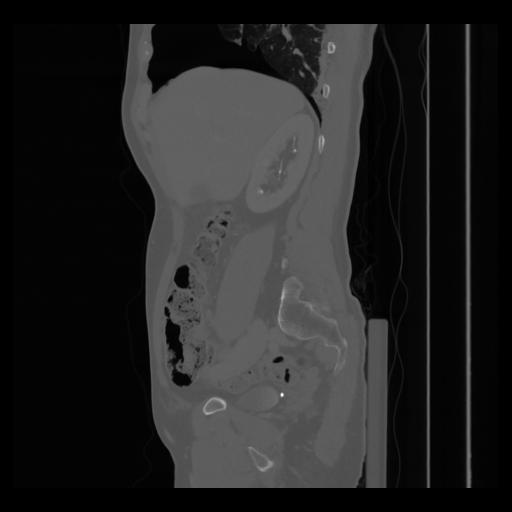

36 CUERPO,CE,Sagittal,3.000,CUERPO,Sagittal,